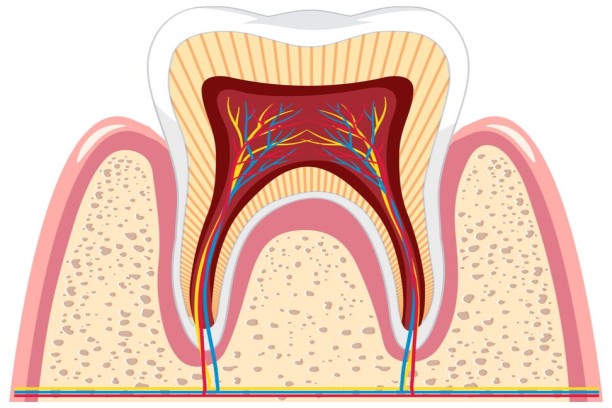

Vital Pulp Therapy

Preserves the healthy pulp tissue in young or damaged teeth.

Apicoectomy

Surgical removal of infected tissue from the root tip to save the tooth.